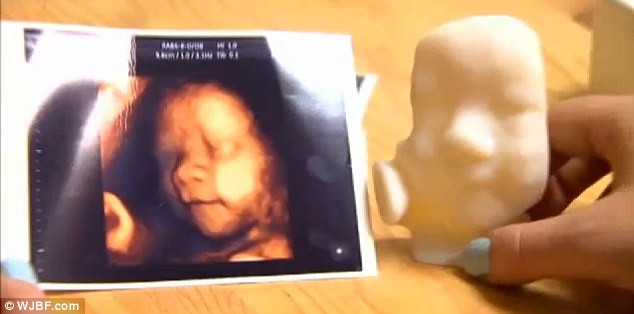

| Khuôn mặt của các bào thai được tạo nên một cách rõ nét nhờ công nghệ in 3D. |

Ngoài ra, công nghệ in 3D này còn có thể dựng nên hình khuôn mặt của các bé một cách rõ nét từng bộ phận (mắt, mũi, miệng, tai..).

“Tôi từng tự hỏi rằng làm sao để biết khuôn mặt con trước khi con chào đời. Nhưng với công nghệ này, tôi đã thấy rõ và cảm nhận được khuôn mặt con tôi khi mang bầu 8 tháng tuổi”, dẫn lời bà Kyodo Aizaka.

Chi phí mà các bà mẹ phải trả để có được mô hình ba chiều của bé sắp chào đời 500 USD.